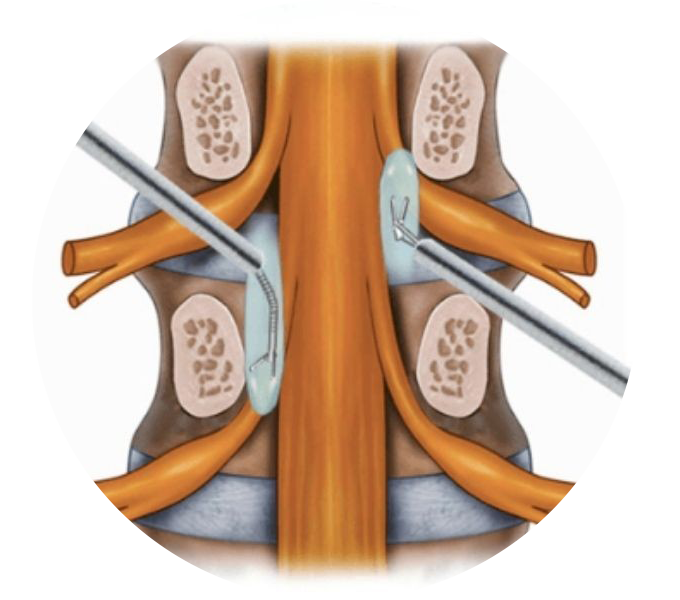

Para lidar com a dor crônica na coluna, é essencial adotar uma abordagem abrangente, que inclua técnicas cirúrgicas avançadas, intervenções minimamente invasivas e uma equipe multidisciplinar dedicada ao manejo da dor. Aliviando a dor crônica na coluna, não apenas melhoramos a função física, mas também elevamos a qualidade de vida dos pacientes.